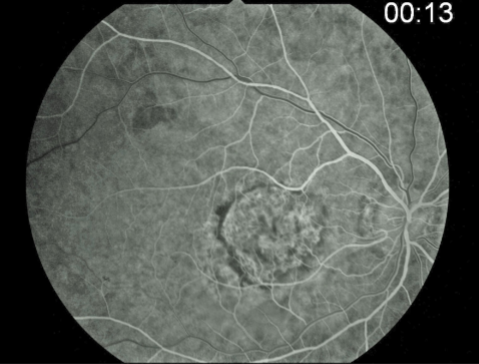

occult stage/Gass type 1

initial blood flow is very slow through CNVM

fibrovascular PED or late leakage of underdetermined source

breaks through Bruch’s but staying sub-RPE

type 1 MNV

fibrovascular PED

late leakage from undetermined source (poorly defined neovascularization)

speckled hyperfluorescence

dye pooling late in study

poorly defined

PCV

similar to type 1 MNV w/ dilated vascular elements (polyps)

MNV type 1

MNV type 1

MNV type 1

MNV type 1

MNV type 1